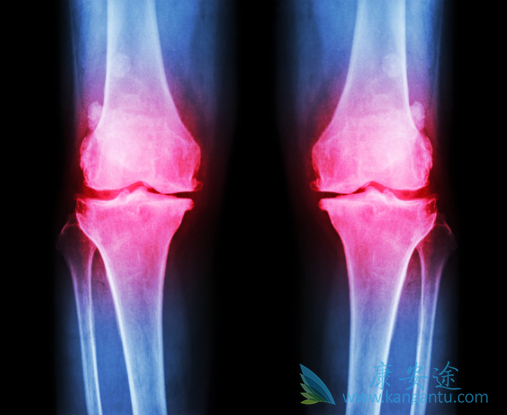

骨髓中某一种或多种的细胞增生特别旺盛,同时增生的细胞形态大致是正常的,主要有:粒细胞增生 - 慢性粒细胞白血病;红细胞增生 - 红细胞增多症;巨核细胞增生 - 原发性血小板增多症;细胞和胶原纤维 - 原发性骨髓纤维化;嗜酸粒细胞 - 慢性嗜酸粒细胞白血病。由于费城染色体和TKI靶向药物的研发,目前慢性粒细胞白血病的治疗已经有很大改观。